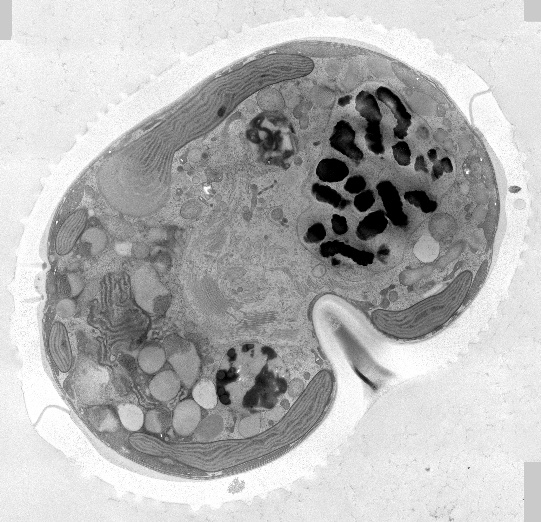

✦可處理200μm厚度的樣品(如動(dòng)植物組織、細(xì)胞團(tuán))

✦保存細(xì)胞器膜結(jié)構(gòu)完整,最接近生理狀態(tài)

動(dòng)物組織、植物組織、三維細(xì)胞培養(yǎng)物、細(xì)菌、病毒等